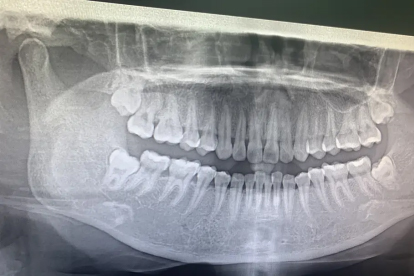

智齿萌出空间不足时易形成水平或倾斜阻生,持续压迫邻牙牙根和周围骨组织。这种机械刺激会导致局部血液循环障碍,引发钝痛或放射性疼痛。临床常见邻牙远中龋坏或牙槽骨吸收,需通过口腔全景片评估阻生程度。对于反复发作者,建议在无急性炎症期拔除阻生智齿。